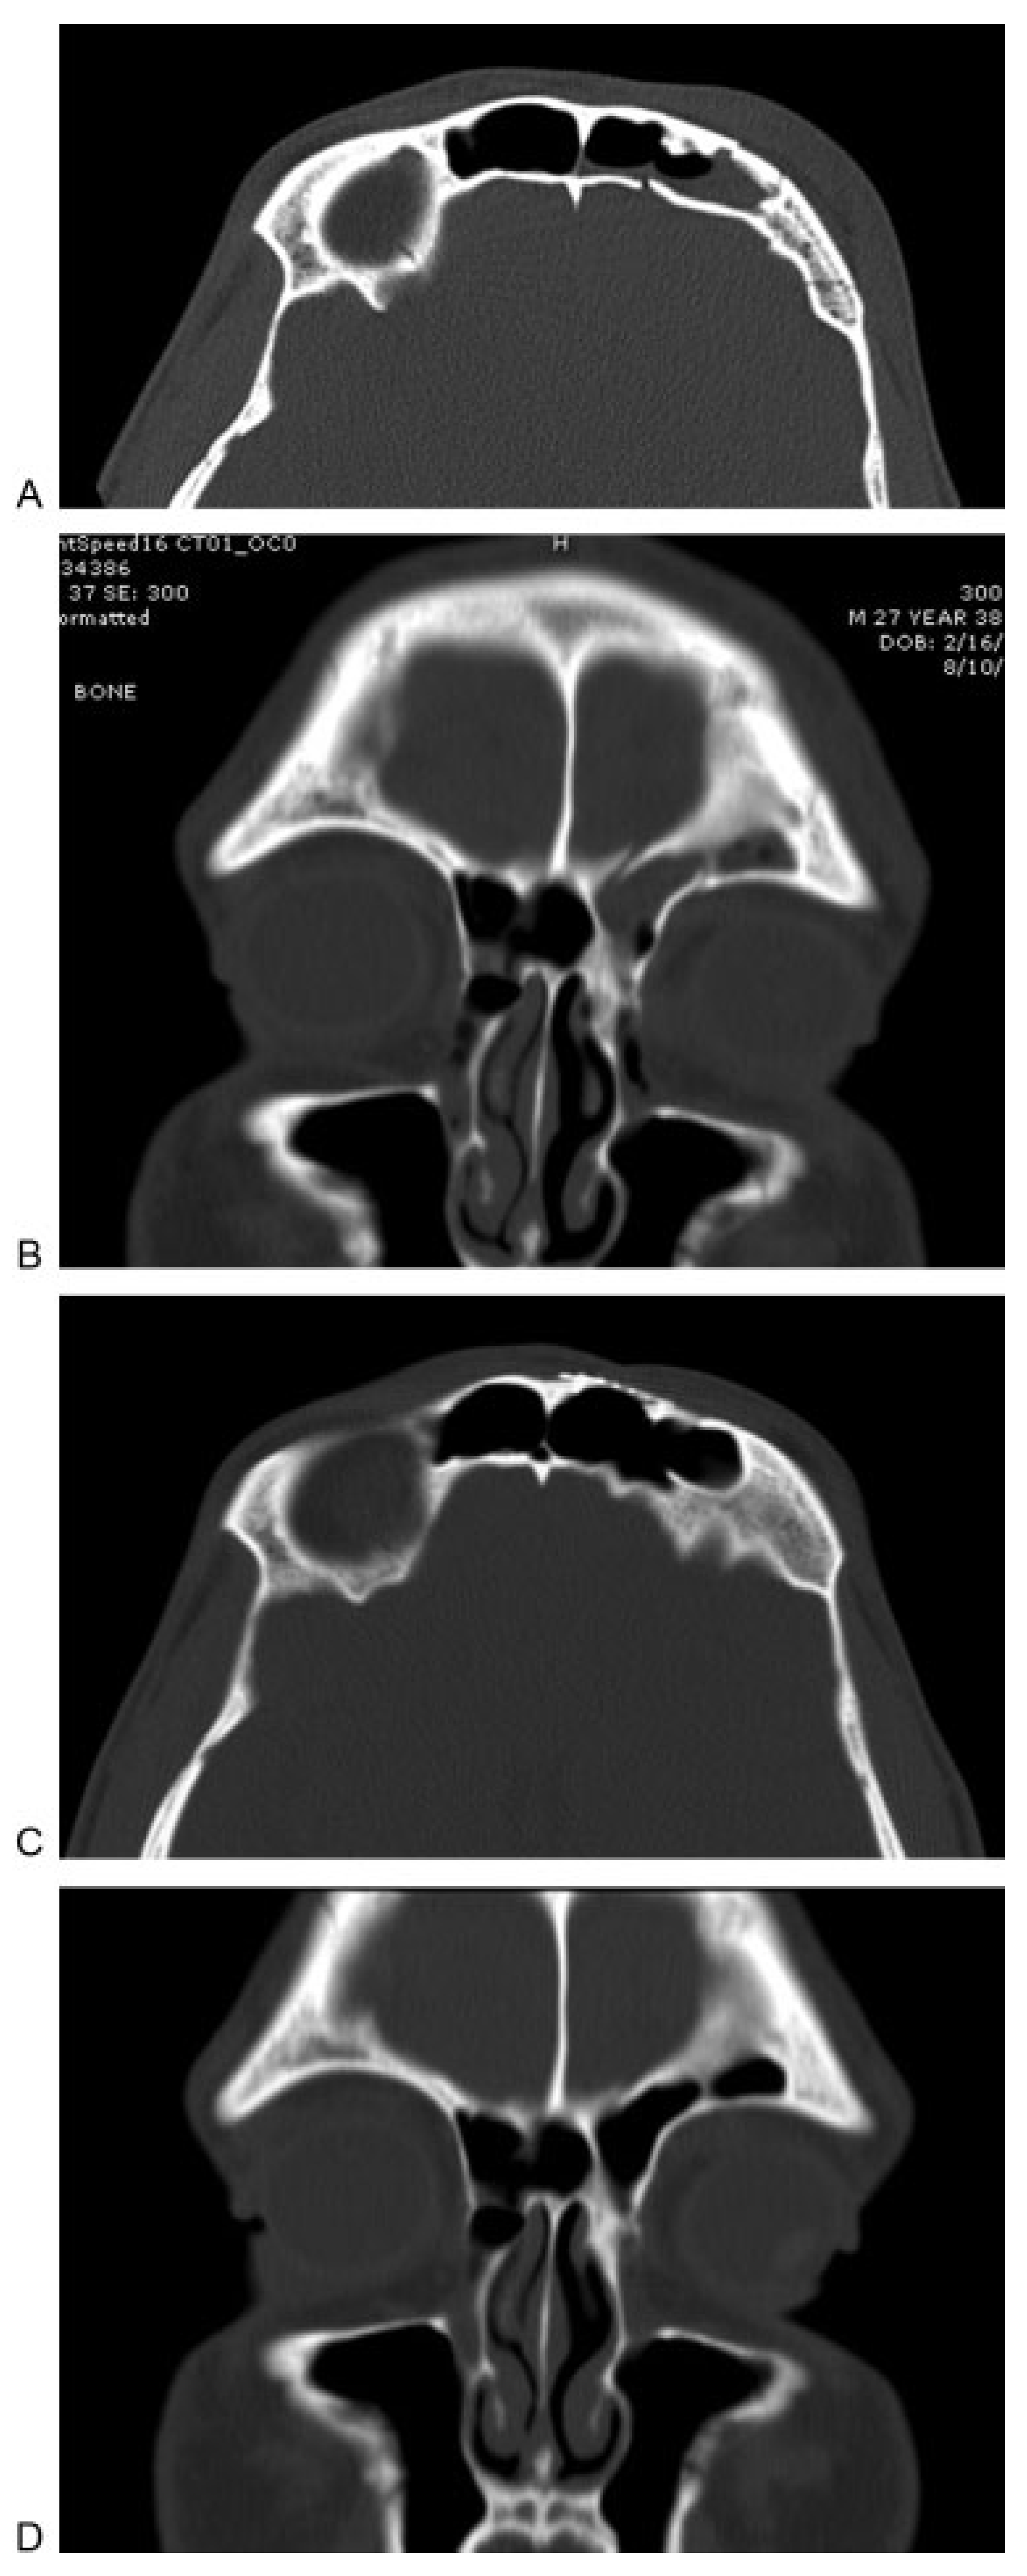

Mucoceles may also arise after obliterative procedures have been performed for trauma. Endoscopic marsupialization can also be used in these cases of delayed mucocele formation. Figure 5 shows images of a patient who developed two separate mucoceles after frontal sinus cranialization for extensive craniofacial trauma. The patient also had severe right orbital trauma at the time of his original injury and had undergone right enucleation. The patient presented with vision loss in his left eye approximately 12 years after his original injury and treatment. After being diagnosed with orbital and intracranial mucoceles, the patient underwent endoscopic marsupialization. The patient has subsequently been followed for 4 years, and continues be asymptomatic and has patent outflow tract to the mucocele cavities (Figure 5).

Figure 5.

(A) Coronal computed tomographic (CT) image showing mucocele that developed in a delayed fashion after extensive frontal sinus trauma and previous cranialization. Image shows mucocele with orbital and intracranial involvement. (B) Coronal CT image showing orbital mucocele. (C) Axial CT image demonstrating two separate mucoceles involving the left frontal and orbital regions. (D) Sagittal MRI demonstrating two distinct mucoceles. (E) Postoperative axial CT image demonstrating aeration of both mucocele cavities after endoscopic marsupialization. (F) Postoperative endoscopic view of the outflow tract of the two mucoceles after complete healing.